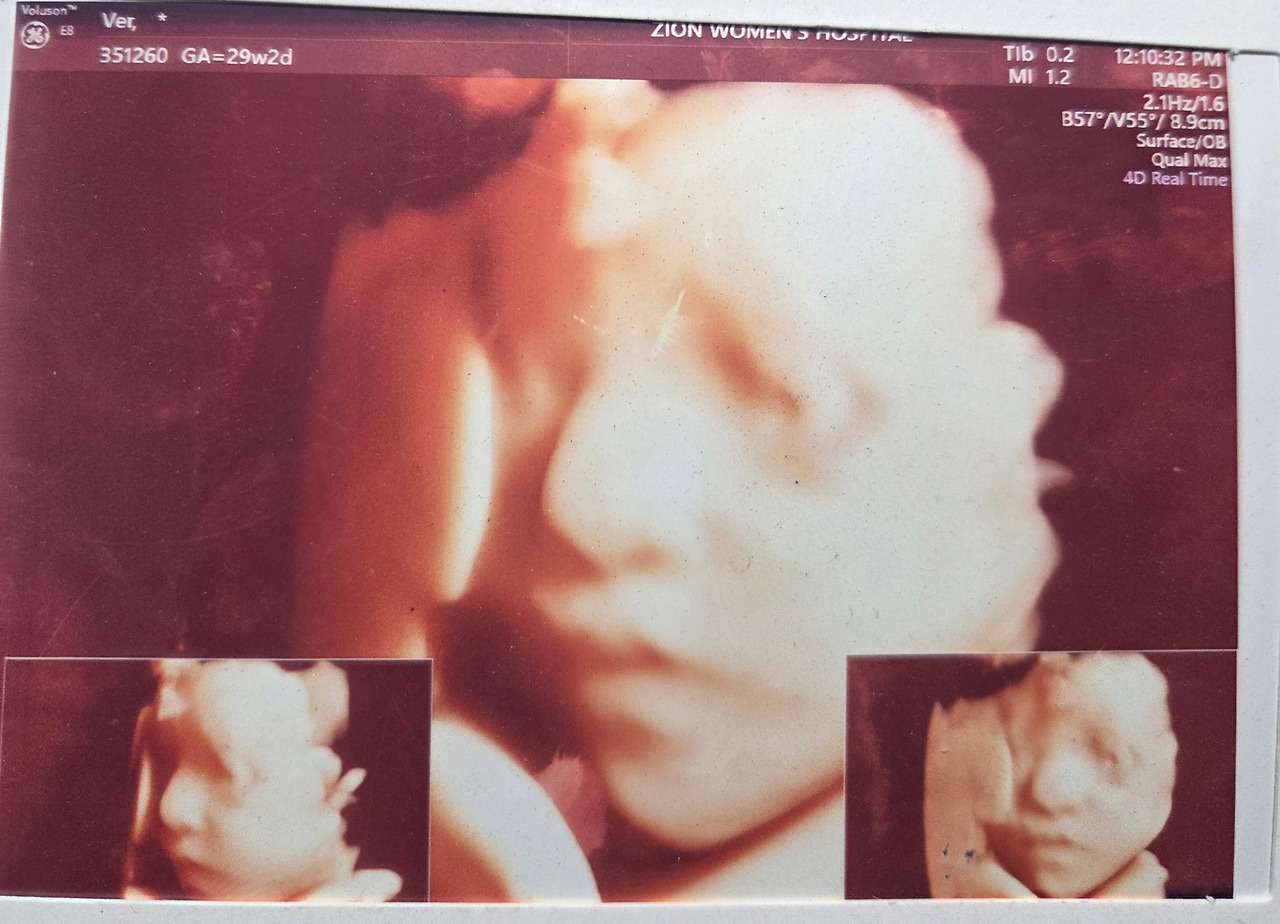

첫째 딸은 전체적으로 나를 닮았지만 눈만큼은 아빠 쪽을 닮아 속눈썹이 길고 속쌍꺼풀이 있는 눈이 초롱초롱했다. 둘째를 임신하고 입체 초음파를 봤는데 사진으로 잘 안 보이는 눈을 제외하고는 첫째와 많이 닮아있었다. 내가 첫째의 눈을 많이 좋아했던 터라, 둘째 아이의 눈도 첫째처럼 크고 예뻤으면 했다. 그런데 아이를 낳고 보니, 아, 불길한 예감은 들어맞았다. 콤플렉스였던 나의 눈을 빼다 박은 둘째 딸. 짧은 속눈썹에 무쌍 눈이었다. 게다가 눈 사이도 약간 멀어 보이는 밋밋한 얼굴. 누굴 탓할 수도 없이 내 눈이라 속으로 이렇게 생각했다.